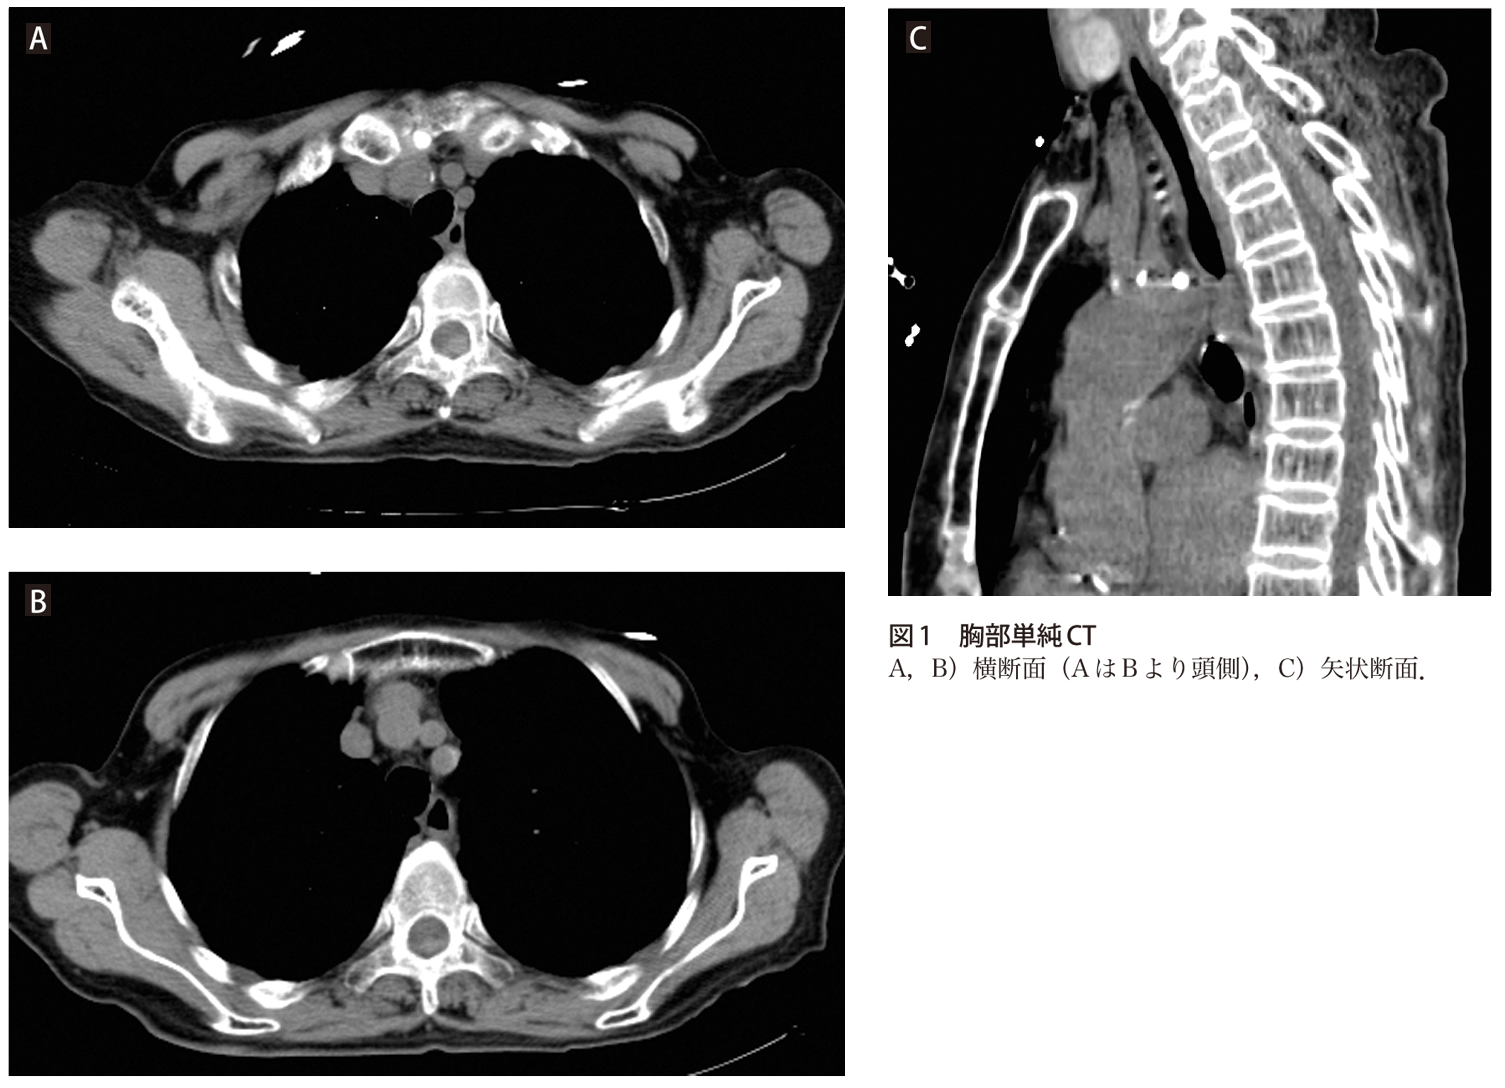

問題 突然の胸背部痛 気づきにくい疾患ですが 目をこらして見てみましょう 実践 画像診断q A 羊土社 レジデントノート 実践 画像診断q A 羊土社 レジデントノート 羊土社